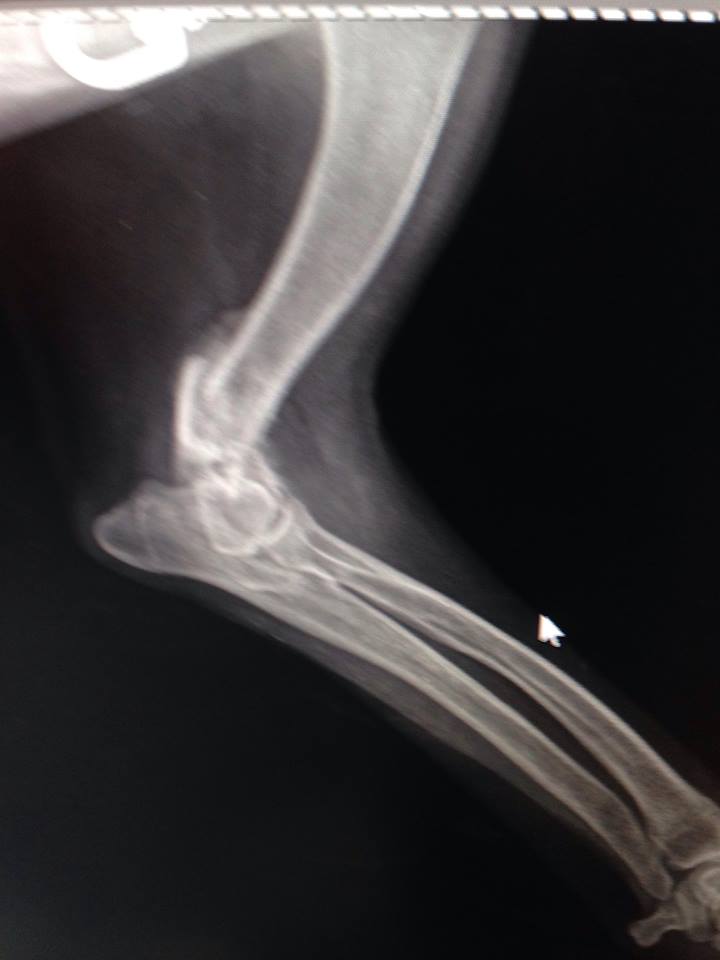

В клинику поступила с жалобами на отсутствие опоры левой грудной конечности. При осмотре обнаружилось, что у собаки нарушены анатомические контуры левого локтевого сустава и при манипуляциях с этим суставом животное испытывает боль.

Рентгенографические снимки в прямой и боковой проекциях показали, что Элли перенесла полтора-два месяца назад перелом латерального мыщелка левой плечевой кости.

Этот перелом не был должным образом пролечен. Собаке нужно было выполнить хирургическое лечение, так как такие переломы лечатся только оперативно. Все внутрисоставные переломы должны быть хирургически собраны максимально точно. Это обеспечивает полноценность работы сустава. Если нет адекватного анатомического сопоставления, будет развиваться остеоартрит, сустав придет в негодность. В данном случае собаке просто наложили гипс. За прошедшее время поверхности срослись в том виде, в каком были при переломе. Сустав полностью был разрушен.